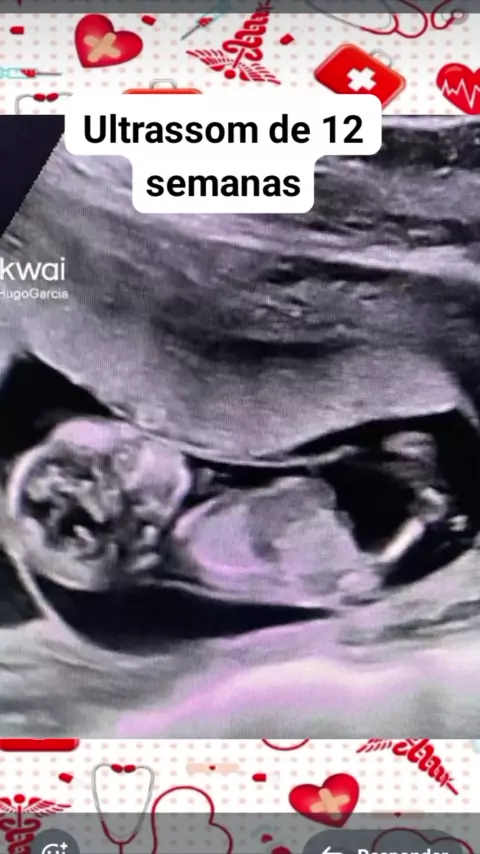

ultrassom de 12 semanas #saude #medicina